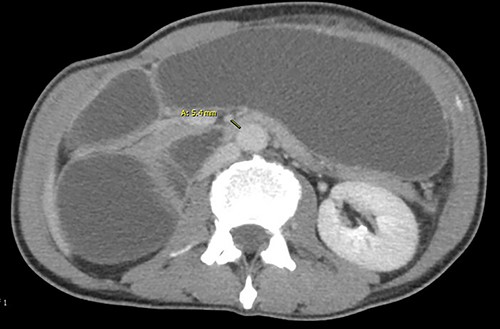

Two days later, the patient returned with emesis and poor oral intake. A repeat CT scan of the abdomen and pelvis with IV contrast was notable for increased fluid distention of the stomach and proximal duodenum with an abrupt transition at the level of the narrowed aortomesenteric interval. The aortomesenteric distance measured 5 mm with an SMA angle of 21 deg, confirming SMA syndrome (Figs 1 and 2). He was admitted, started on total parenteral nutrition (TPN). Preoperative endoscopy was performed revealing an area of constriction in the third part of duodenum. The duodenum was dilated without lesions or strictures; however, the endoscope could not traverse this area.

Angle between superior mesenteric and aorta artery measuring 21. deg.